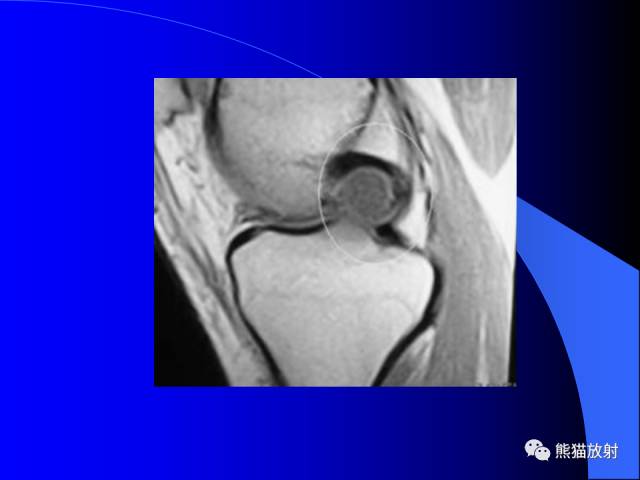

膝关节周围囊肿MRI

膝关节周围囊肿是较常见的病变,可以是原发的,多见于青年及儿童,囊内容物通常是黏液;也可以是继发的,多与关节腔相通,内含一般黏性的滑液,常继发于膝关节骨关节炎、类风湿关节炎、非特异性滑膜炎、半月板损伤、髌骨软骨软化症等。

腘窝囊肿是膝关节周围最常见的囊肿。